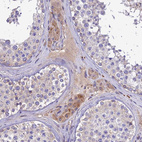

Immunohistochemical staining of human liver shows moderate cytoplasmic positivity in hepatocytes.